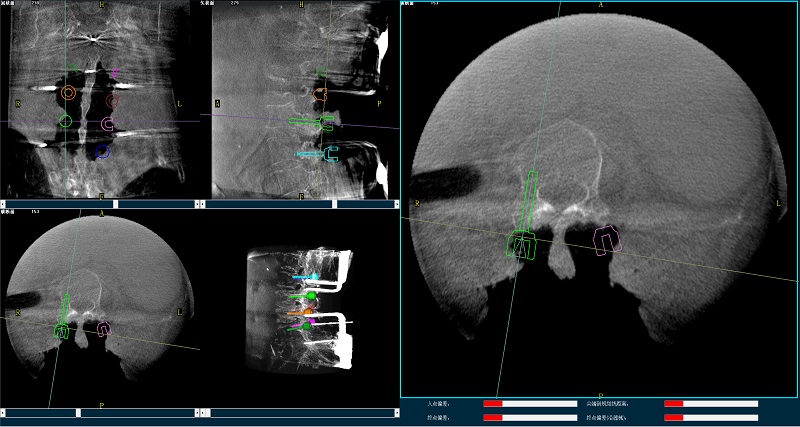

三維圖像

(2)使用普愛醫療平板三維C形臂掃描患者,得到術中三維圖像并傳送至骨科機器人導航系統。骨科機器人導航系統基于高清術中三維圖像進行手術規劃。

手術規劃圖像